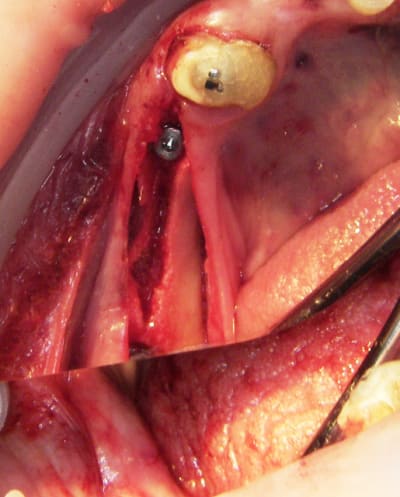

2:

Ostéotome "lame" angulé

lame 15 (fréquent dans ce cas )

Ostéotome droit

tous sont manipulés avec douceur, mais aussi impactés avec le maillet chirurgical

3:

de nouveau ostéotome "lame" angulé

Ostéotome droit, plus étroit que le premier.